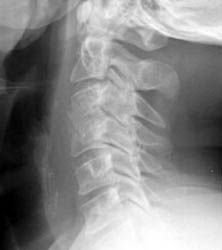

Instability

48 y.o. male with a history of alcohol abuse, depression and degenerative joint disease who is complaining of severe pain in his right neck and shoulder radiating down to his right third and fourth digit. The patient underwent anterior cervical disc fusion. Four months after the initial surgery, the patient still had pain but this time numbness was on flexion mainly and localized to the C5 region.

Lateral flexion and extension radiographs taken 6 months after surgery demonstrate incomplete graft incorporation (delayed healing). Furthermore, with flexion there is anterolisthesis of C4 on C5 (one level below the fusion) by 2-3 mm.